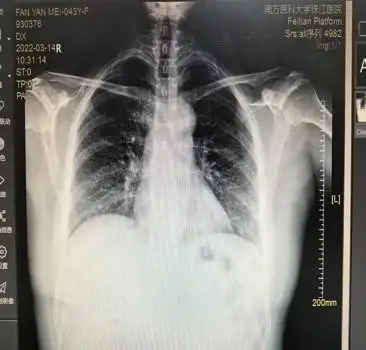

医学影像学-循环系统实习 心脏形态异常-普大型心脏 心脏向两侧均匀

狭隘普大心图普大型心该例为心包积液心胸比率约064自我凹陷正常心脏

( )a:"中间型"心脏b:"横位型"心脏c:"主动脉瓣型"心脏d:"普大型"

心肌病(普大心)a.